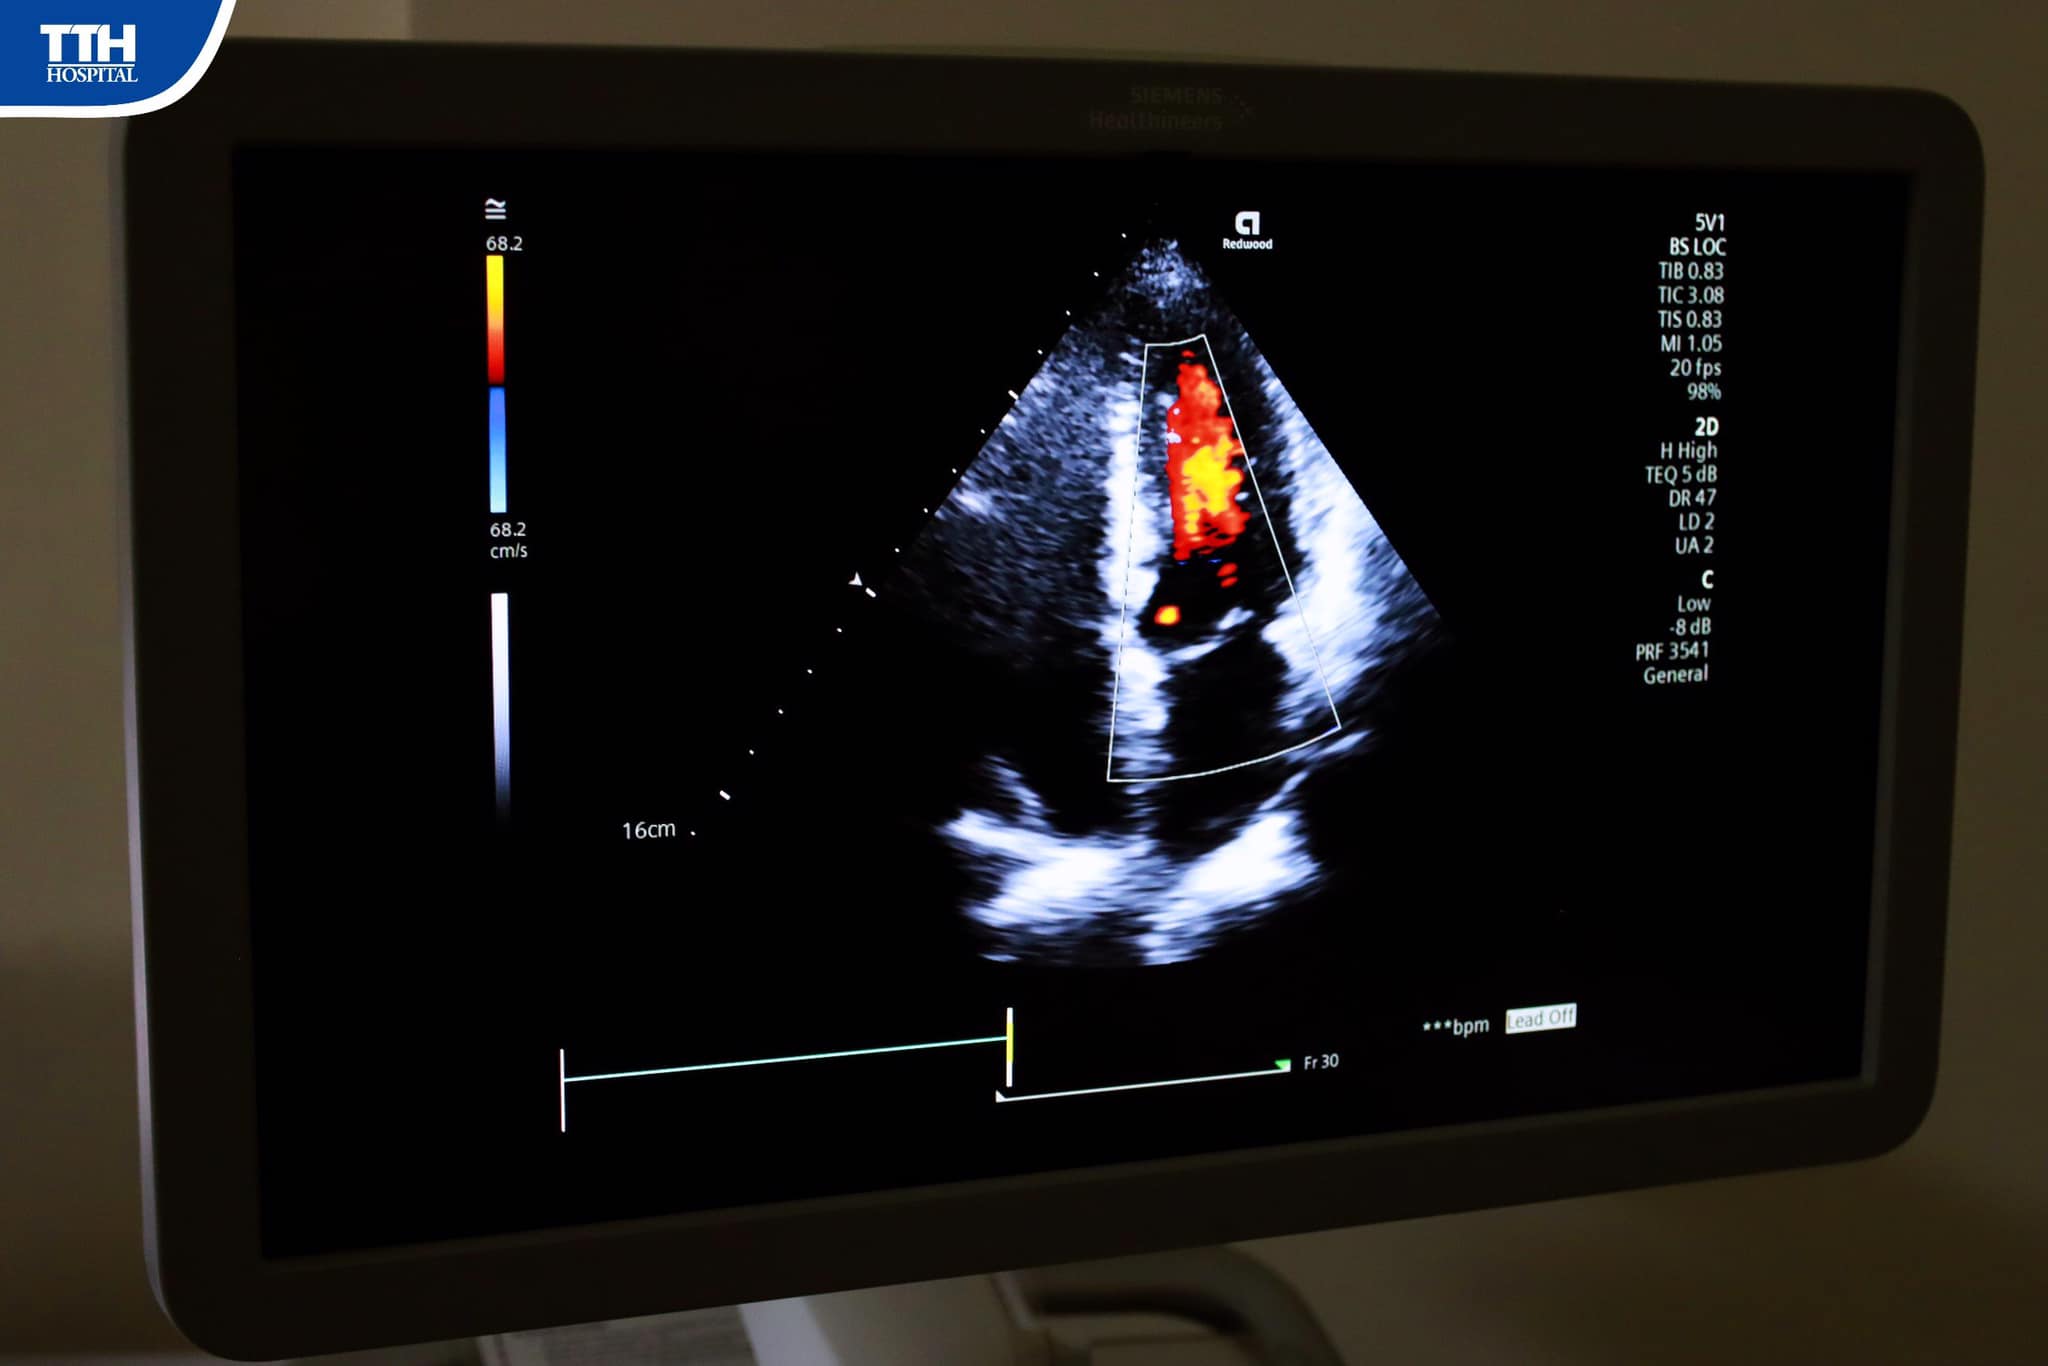

Ngày 11/11/2023, Bệnh viện Đa khoa TTH Hà Tĩnh đã tổ chức chương trình “Khám Tim mạch cùng chuyên gia” Ths.BSNT Bùi Nguyên Tùng, Viện Tim Mạch Quốc gia, Bệnh viện Bạch Mai.

Tại đây, khách hàng được Ths.BSNT Bùi Nguyên Tùng, chuyên gia Nội tim mạch, có hơn 10 năm trong lĩnh vực khám nội khoa tim mạch, can thiệp tim mạch, bệnh lý van tim, suy tim, mạch vành, mạch máu ngoại biên trực tiếp thăm khám.